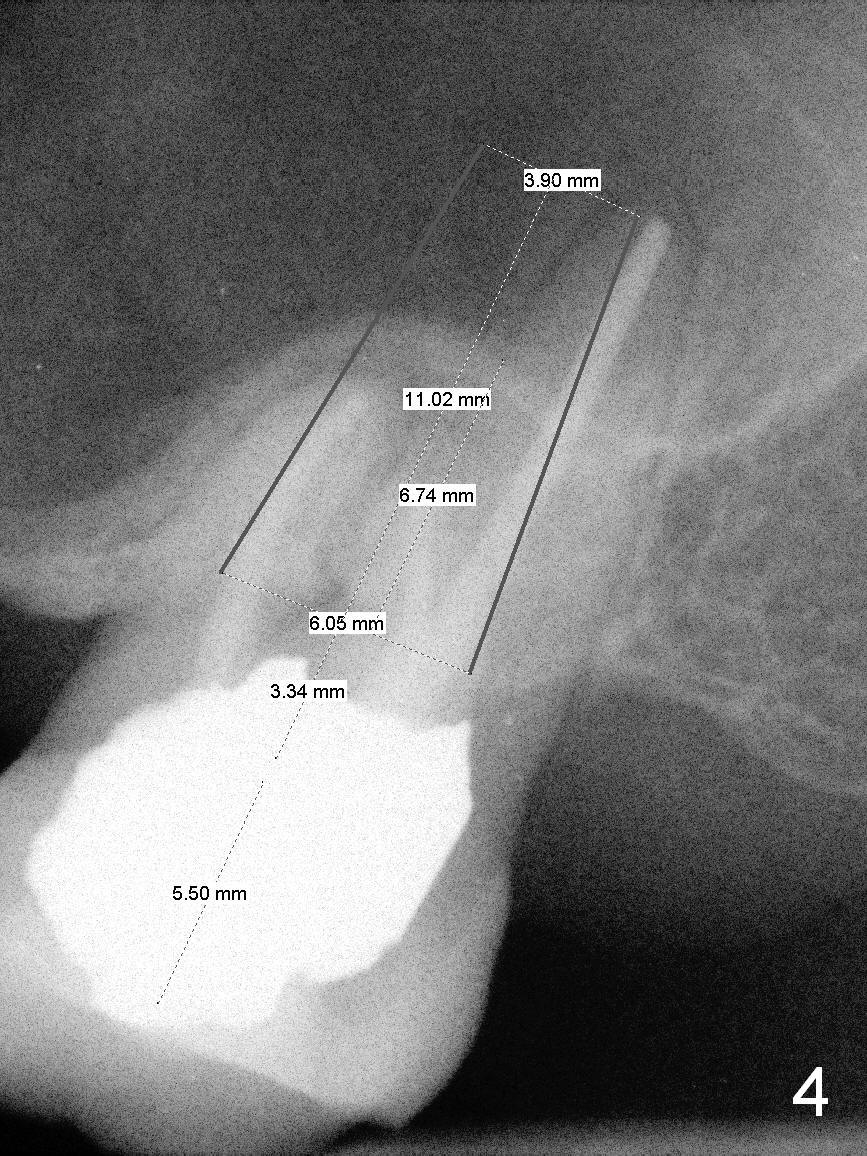

A 60-year-old man requests implant at #15, since the tooth with distal subgingival caries has kept fracturing in the last 4 years (Fig.1,2). Metronidazole will be used for socket disinfection. Since the socket is most likely large and single (fused roots), a large IBS implant (Fig.3,4: 6 or 6.5x9 or 11 mm) is to be placed following initial 7 mm depth of drilling or bone expansion (Fig.4). Prepare bone graft for sinus lift and gap closure. His bone is soft at #10; underprep is necessary at #15. An abutment is expected to be 6x4(3) mm (Fig.4). Since he is partially edentulous, an immediate provisional should be large enough to close the socket, but small enough not to be interfered with the partial denture on and off. Take photos of #10 to show no metal show.